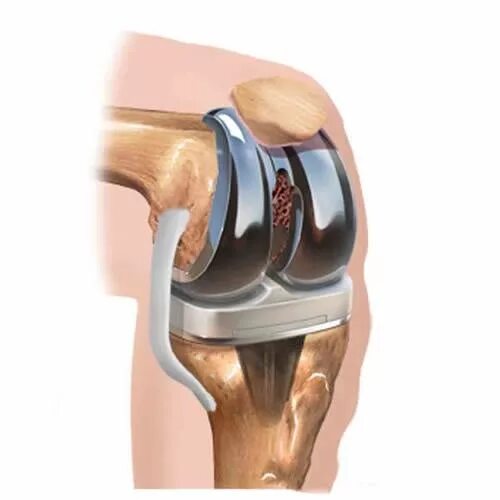

После тотального эндопротезирования коленного сустава